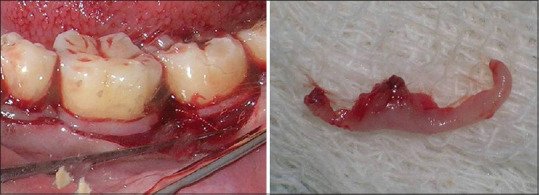

Materials and methods: The study group was divided into the four groups of 25 patients in each group. Group A were patients having healthy periodontium and without any systemic diseases. Group B were patients having periodontitis without any systemic diseases. Group C were patients having both periodontitis and DM. Group D were patients having only DM without any periodontitis. The VEGF levels were graded into three grades of 0, 1 and 2. They were evaluated through immunohistochemistry in tissue samples obtained from all the groups.